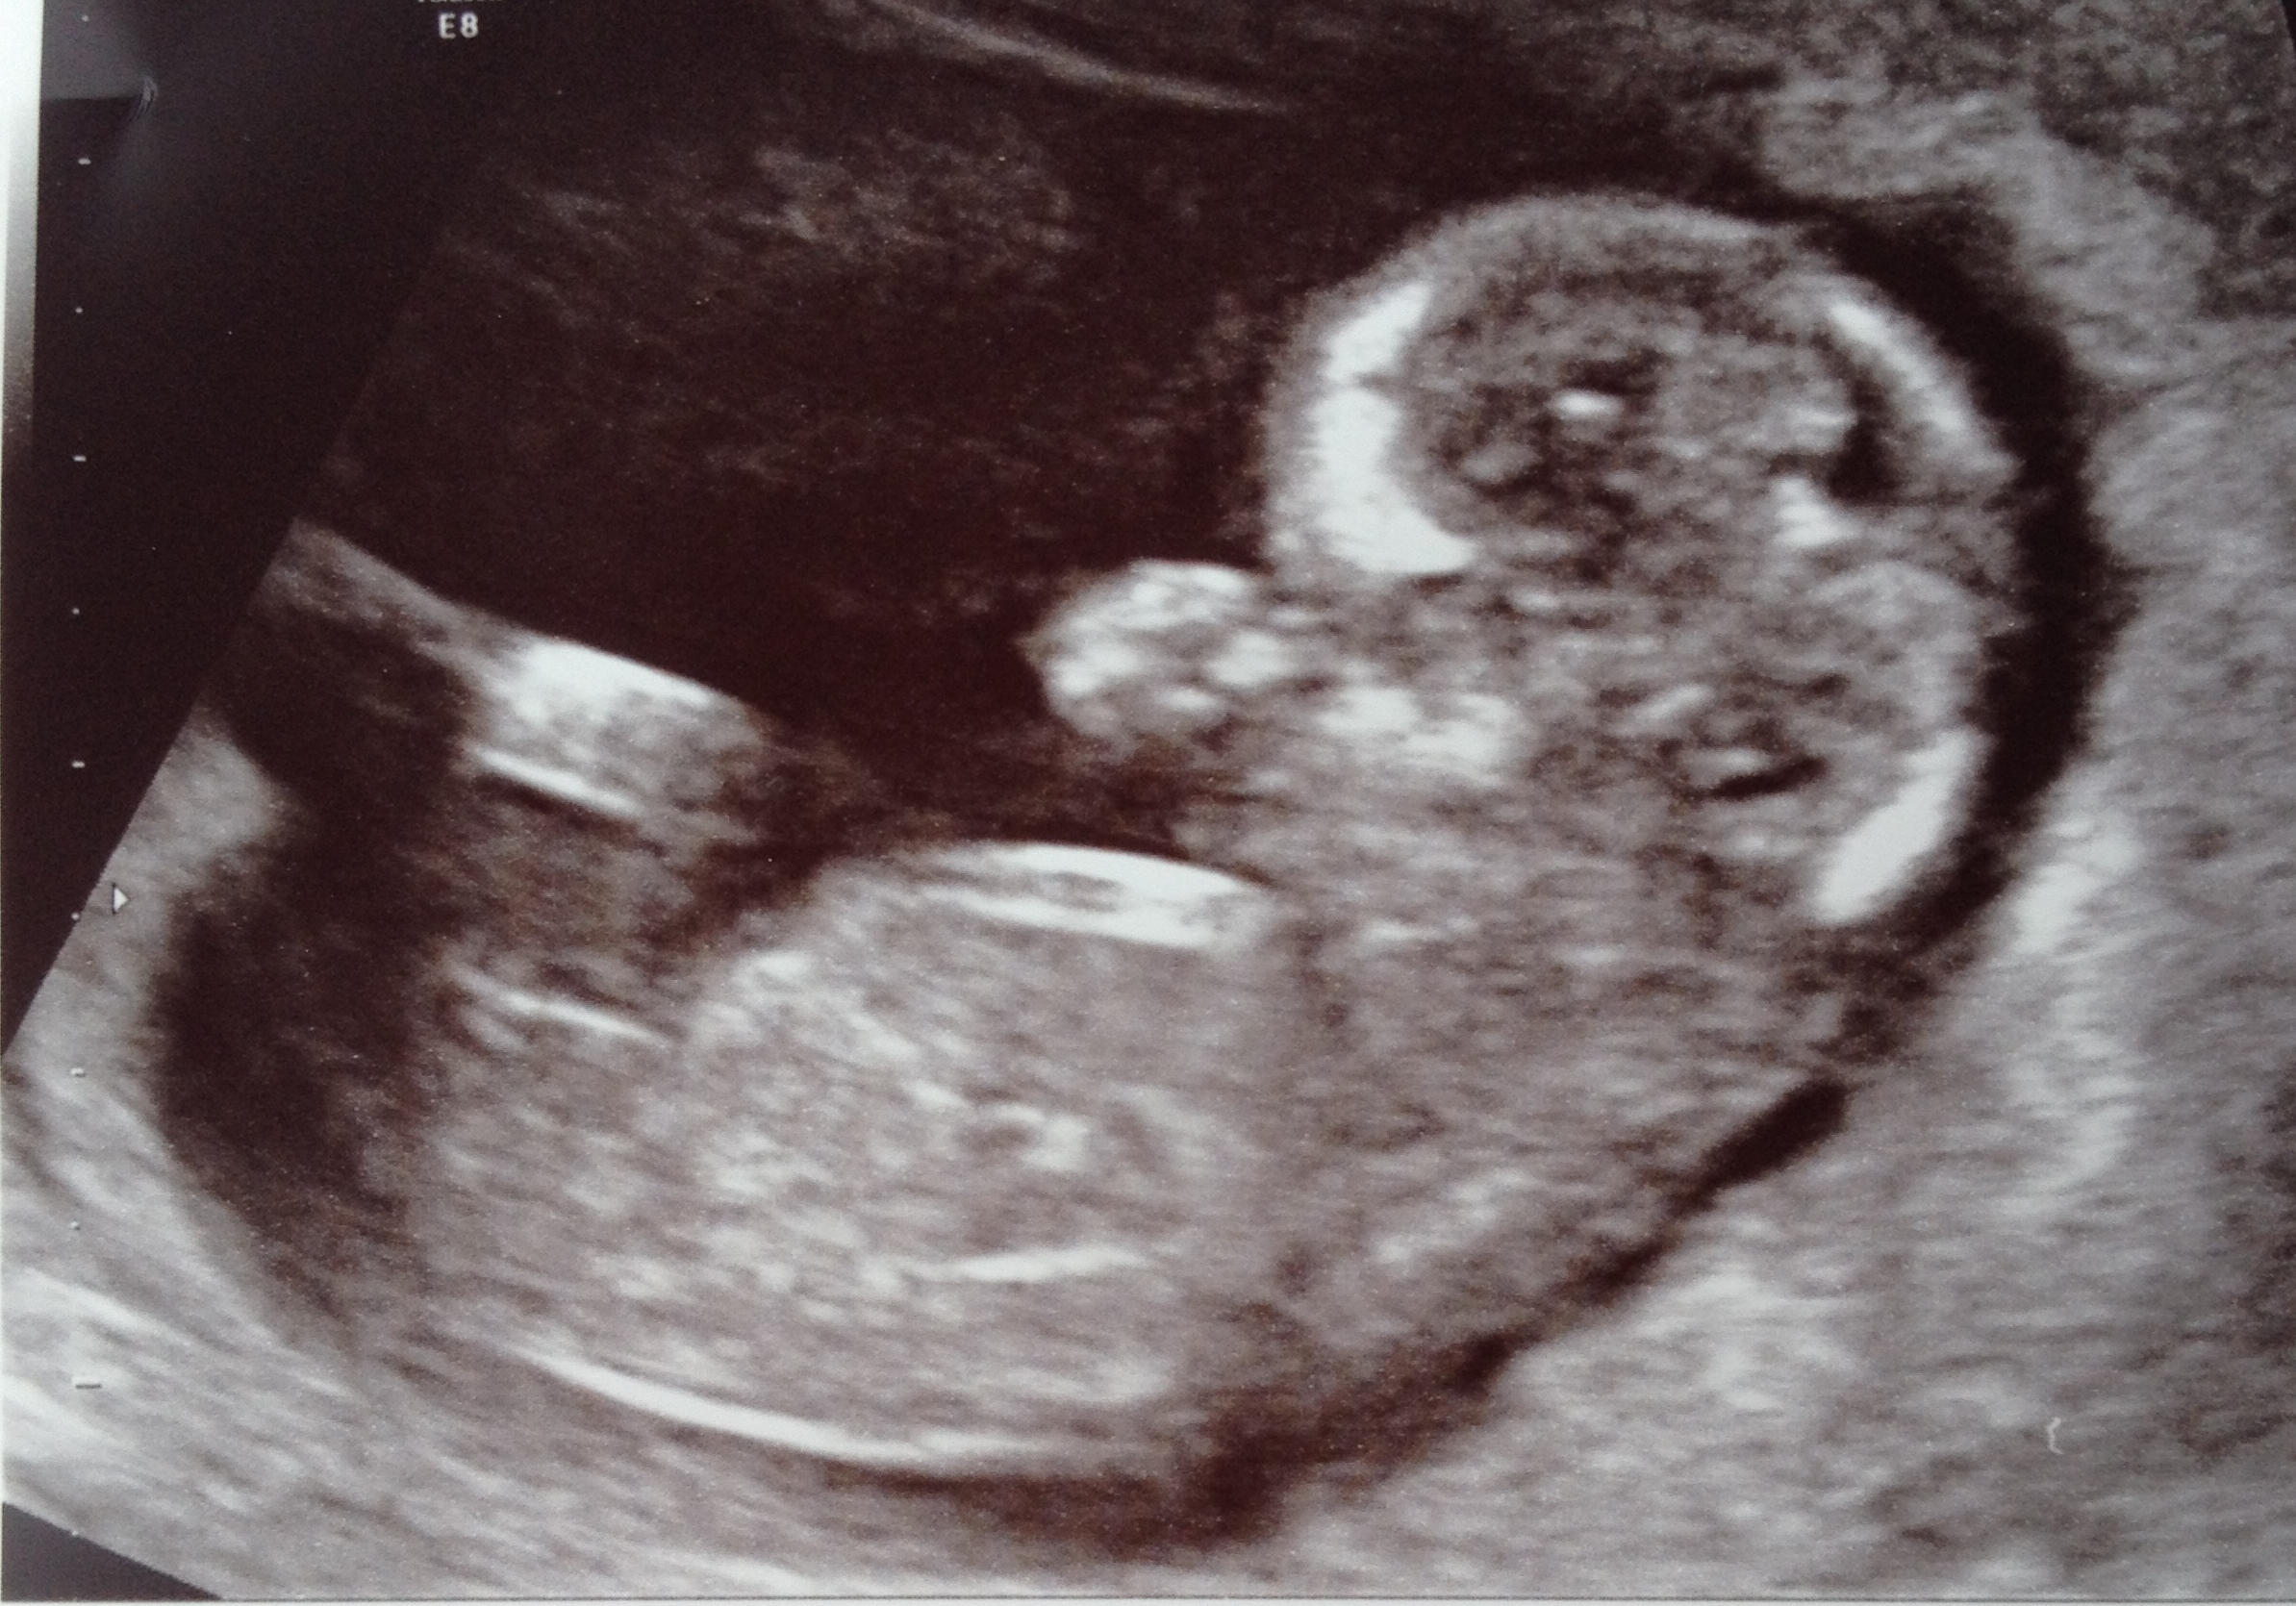

Had a scan at 12+5 with a really clear nub! My immediate guess was girl for the nub as its in line with the spine (feel free to correct me if I'm wrong!), I have no clue what to look for with skull theory!

Attachment 17736

leaning girl but that angle is hard with baby curved!

I agree the curve of baby's spine is not giving us a good idea of the angle of the nub- so a tentative girl lean bc it's long past the bum but would be more confident if spine was flat

I'm leaning boy too, there's a bit of an angle happening there.

I'm seeing a bit of angle too. But gestation would suggest that a boy would be much more angled at this stage. I'm not really confident either way. Sorry!

Hi I see you're scan pic on one of the other sites and guessed blue and then gave more of a pink lean with the second pic you put up, but i keep looking at yours as the more I look the more I feel pink! I think the first pic (second pic on here) baby is very curled so is more deceptive with the rise, so I'm changing my mind and going for pink! GL xx